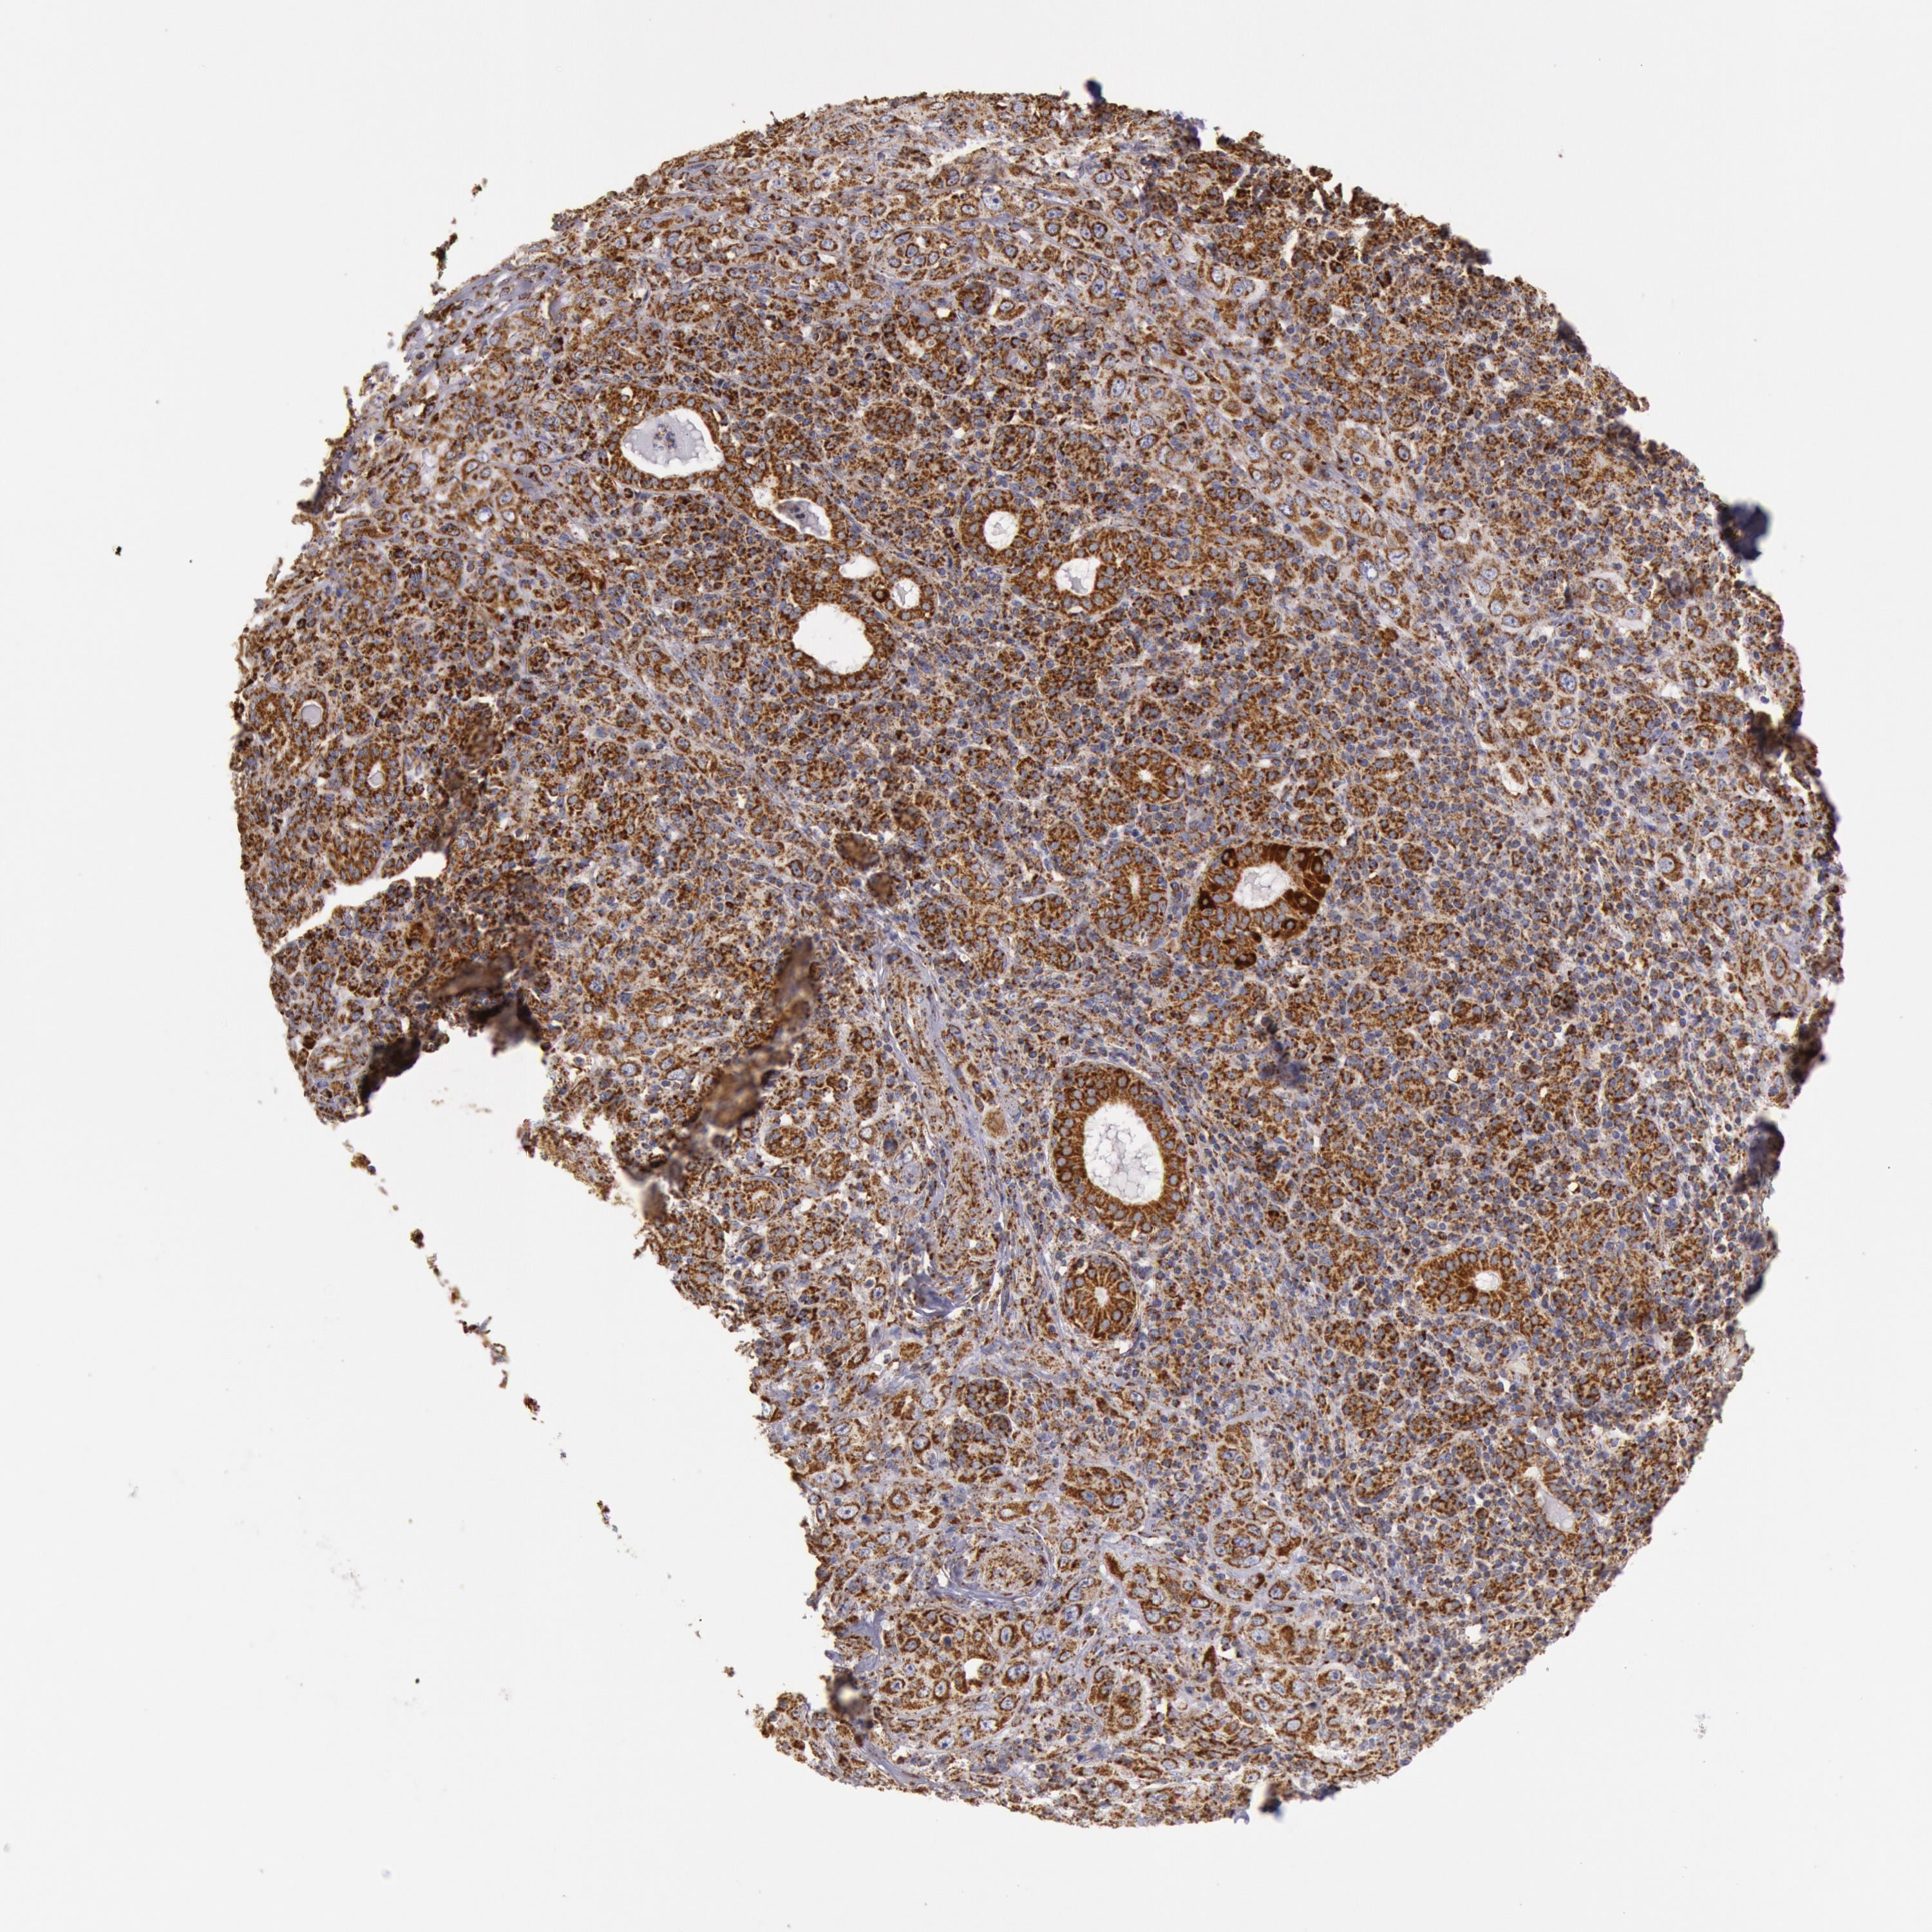

SKIN CANCER - Protein expressioni

A mouse-over function shows sample information and annotation data. Click on an image to view it in a full screen mode. Samples can be filtered based on level of antibody staining by selecting one or several of the following categories: high, medium, low and not detected. The assay and annotation is described here.

Antibody stainingi

Antibody staining in the annotated cell types in the current human tissue is reported as not detected, low, medium, or high, based on conventional immunohistochemistry profiling in selected tissues. This score is based on the combination of the staining intensity and fraction of stained cells.

Each image is clickable and will lead to virtual microscopy that enables deeper exploration of all samples and also displays staining intensity scores, fraction scores and subcellular localization as well as patient and tissue information for each sample.

Antibody HPA001247

Staining

High

Intensity

Strong

Quantity

>75%

Location

Cytoplasmic/membranous

Squamous cell carcinoma, NOS

Basal cell carcinoma